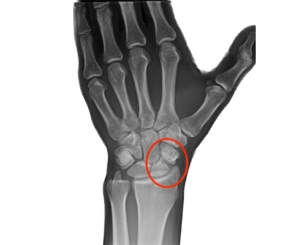

É uma fratura no osso escafóide do punho, frequentemente causada por uma queda sobre a mão estendida.

É a não consolidação de uma fratura no osso escafóide do punho, um problema comum que pode ocorrer se a fratura não for diagnosticada ou tratada corretamente.